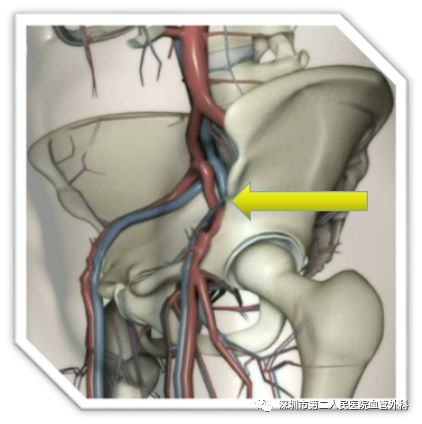

什么是血栓呢?简单地说,就是心脏和血管内血液凝结而成的血凝块。当我们的血管壁受到各种原因的损伤后,内膜下的胶原暴露于血液当中,激活了凝血系统,引起了血小板的聚集、黏附在受损的血管壁上,并吸引更多的血小板和白细胞聚集和黏附,和纤维蛋白一起形成珊瑚状的固体“骨架”。“骨架”间的血液变得缓慢甚至停滞,血小板、白细胞、红细胞凝集在一起,形成完整的血栓(图2)。

由于血流被血栓阻断,如果得不到及时治疗,血栓就会向血管的近远端蔓延,症状加重。血栓形成以后,在机体自身的各种溶栓机制的作用下,很小一部分血栓会完全溶解消失,血管恢复通畅,大部分血栓会发生机化收缩,损伤血管的瓣膜和内壁,加重血管壁的损伤。

图2 电镜下形成血栓的纤维骨架和血细胞